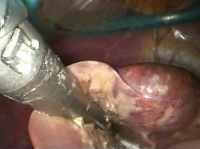

Πρόκειται για γυναίκα ασθενή 32 ετών η οποία, στα πλαίσια γυναικολογικής λαπαροσκόπησης, διαπιστώθηκε ότι έφερε στο 4ο ηπατικό τμήμα ευμεγέθη βλάβη. Η τριφασική MDCT ήπατος που ακολούθησε ανέδειξε μονήρες αδένωμα μεγέθους 5 cm σε επαφή με τον ηπατοδωδεκαδακτυλικό σύνδεσμο (εικόνα 1). Η ασθενής υποβλήθηκε σε λαπαροσκοπική (HALS) εκτομή του ηπατικού τμήματος 4b και σε χολοκυστεκτομή (εικόνα 2). Η διατομή του ηπατικού παρεγχύματος έγινε με τη χρήση αυτορυθμιζόμενης διπολικής διαθερμίας (εικόνα 3) και αυτόματου λαπαροσκοπικού αγγειακού κοπτοπάπτη (εικόνα 4). Διενεργήθηκε συμπλησίαση της επιφάνειας διατομής με τη χρήση ραμμάτων (εικόνα 5). Το παρασκεύασμα δεικνύεται στην εικόνα 6. Η ασθενής έλαβε εξιτήριο την 3η μετεγχειρητική ημέρα.